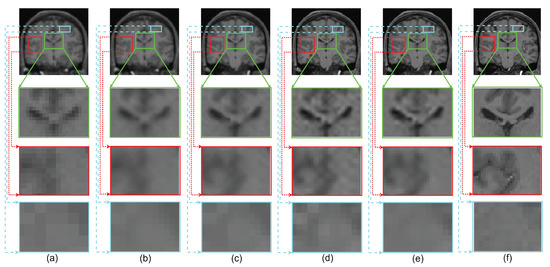

To emphasize the significance of reconstruction of uncommon image details in the proposed SR method, we chose a real MR image volume with a cavernoma and improved its resolution by factor 2, as shown in Figure 11. It can be observed that the LRTV [12] approach in Figure 11d reduces the blur as compared to interpolation and NLM3D [13] in Figure 11b,c, but tends to produce staircase effect. It can be observed that the tissue boundaries and image details inside the cavernoma, shown in the red box, are more clear and distinct for the proposed method. In addition, the skull outlines can be seen to be well defined (in the sagittal plane) in the case of the proposed algorithm (see Figure 11e) as compared to existing methods.

Figure 11.

Illustration of super resolution results for structural deformity cavernoma in real MR images, by different algorithms: (a) nearest neighbor, (b) spline interpolation, (c) non local means in three dimensions (NLM3D) [13], (d) low rank total variation based method (LRTV) [12], (e) the proposed approach, and (f) the original HR image. Each slice in axial, sagittal, and coronal planes is shown. The zoomed version of the cavernoma region from the coronal slice is highlighted in red rectangle. Please zoom for better visualization.